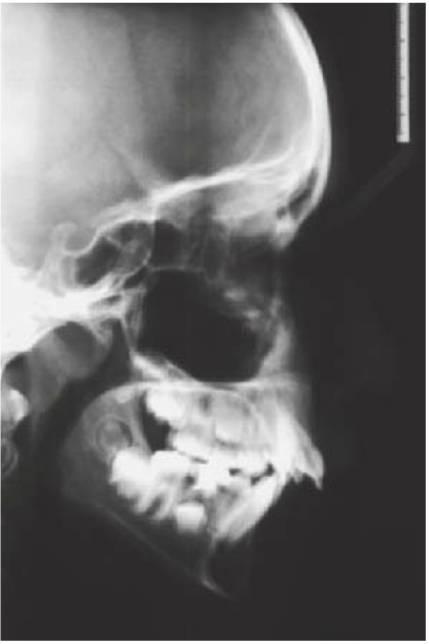

- Cefalograma lateral: resulta eficaz para valorar la discrepancia esquelética al inicio del tratamiento. El trazado y el análisis cefalométrico posterior en una radiografía subsiguiente contribuirán a la planificación y diagnóstico del tratamiento, y todas las imágenes pueden también utilizarse como línea de referencia para supervisar el crecimiento futuro.